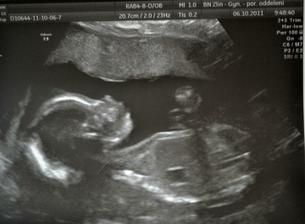

Naše miminko ♥